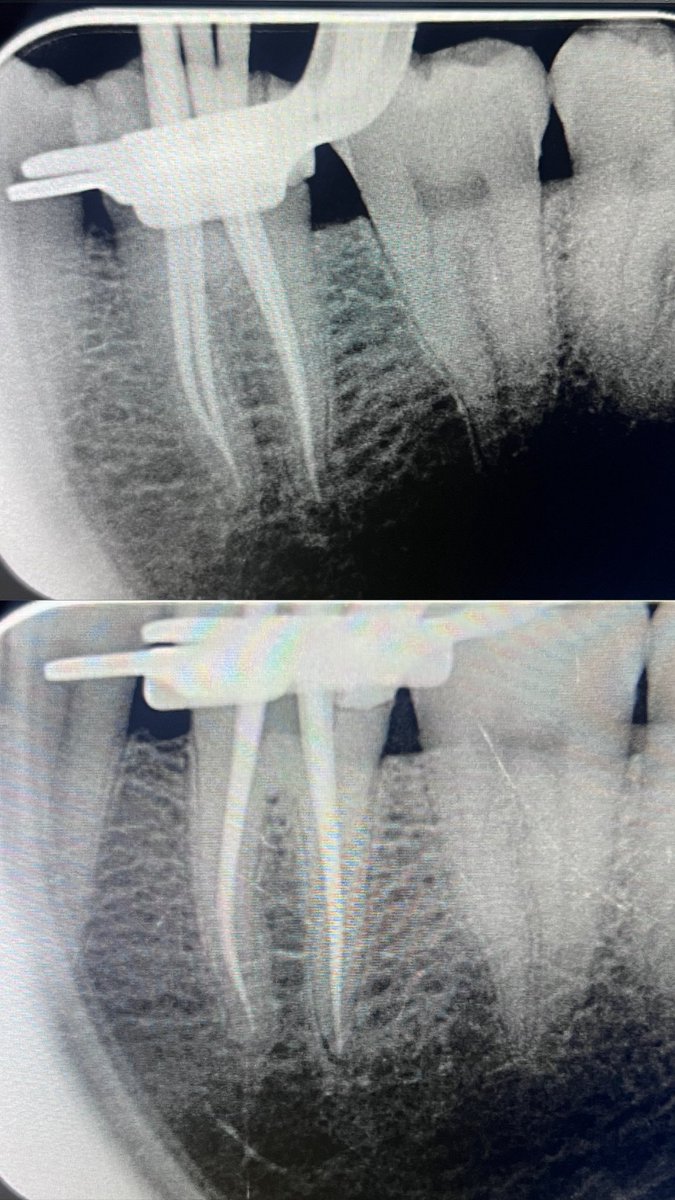

حالة جديدة اليوم ❤️

Root Canal Treatment for #36

The patient complained of severe pain,after examination we decided to do RCT.

Dx: SIP,NAP

ML wall is replaced then started RCT.

Single Cone and BC Sealer are used